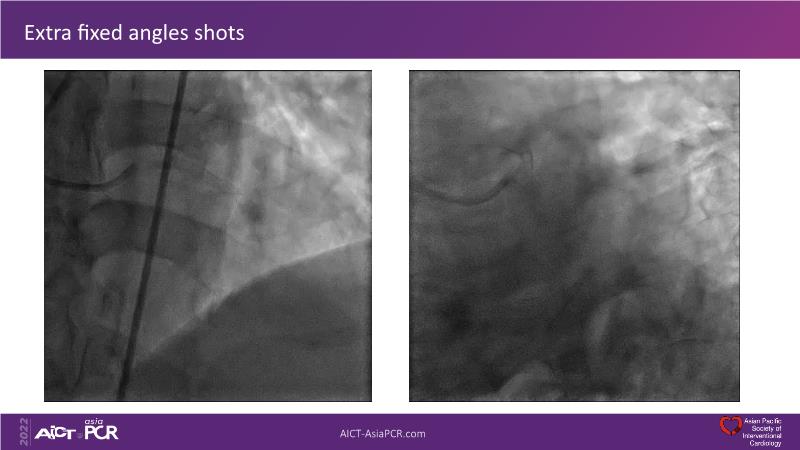

In this session, presenters describe how to use IVUS and physiology in the assessment of left anterior descending and/or left circumflex ostium in distal left main disease. Discover in the second part the general principles and clinically validated strategies for ultralow contrast coronary angiography and zero contrast percutaneous coronary intervention.

- To learn to create contrast-free IVUS and iFR co-registration roadmap for stent enhancement and optimal treatment